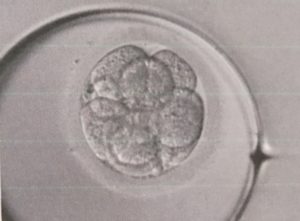

前回は三回目の採卵→体外受精からの、2個新鮮胚移植をしてみたというご報告を書きました。

これが功を奏したのか、、、hcg600で妊娠4週目という嬉しい判定が出ました。